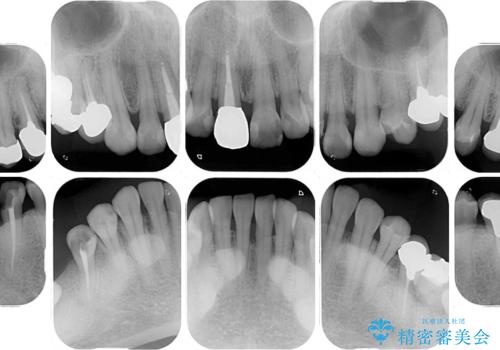

- 右下の欠損部の治療を希望して来院された患者様です。

部分矯正を行った後にインプラント埋入と手前の歯の根管治療を行い、その後補綴治療を行うこととしました。

治療途中より、上の歯や反対側の銀歯、上顎前歯の色合いや下顎前歯のデコボコが気になってきたため、全てを治療することとしました。